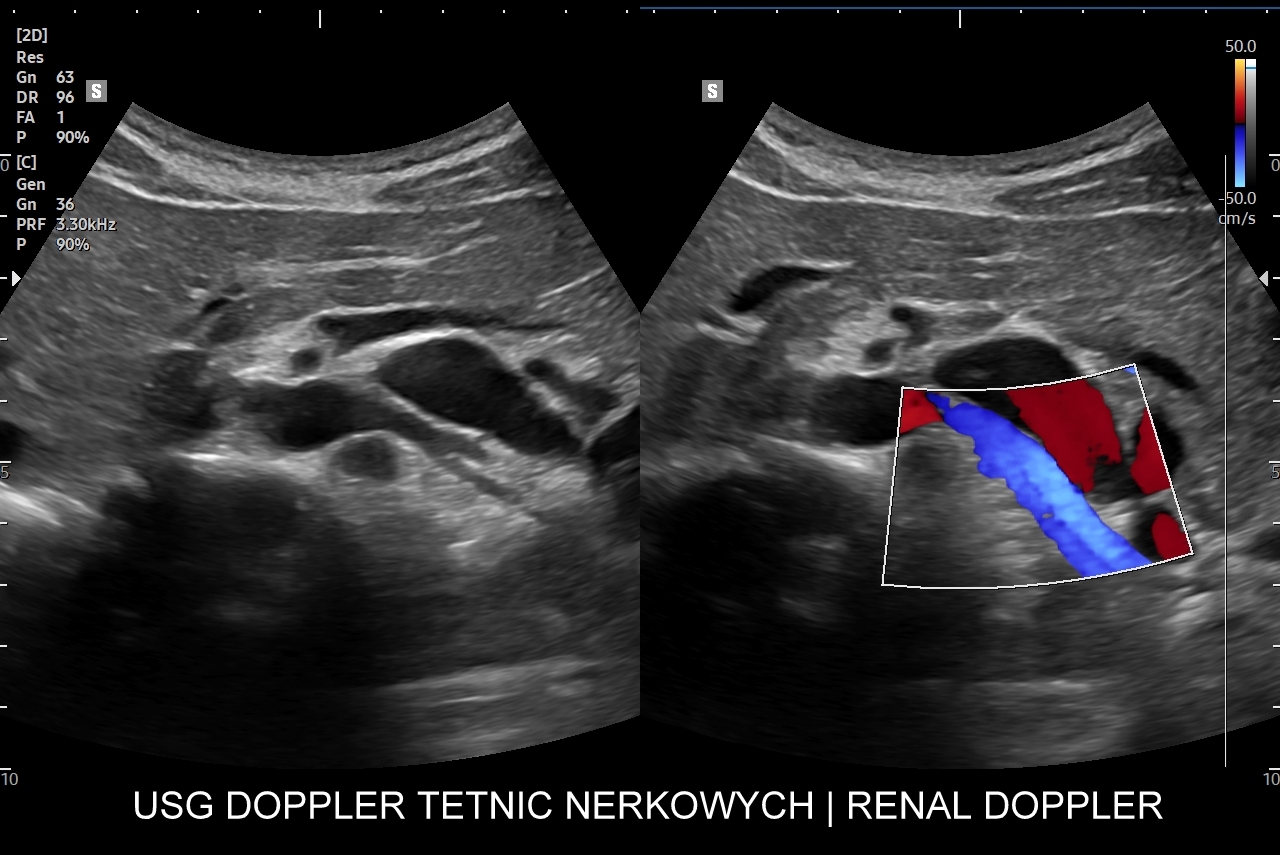

Doppler przepływów nerkowych (USG przepływy nerkowe) jest połączeniem badania obrazowego USG z badaniem funkcjonalnym nerki, jej naczyń tętniczych i żylnych oraz globalnie stanu układu krążenia. Najczęstszym wskazaniem do wykonania USG Doppler tętnic nerkowych, będącego częścią USG Doppler przepływów nerkowych, jest nadciśnienie tętnicze i poszukiwanie jego przyczyn w postaci zwężenia tętnic nerkowych, które mogą wystąpić w odcinku przednerkowym, jak i wewnątrznerkowym. Wykonanie oceny dopplerowskiej nerki jest szczególnie ważne w przypadku wystąpienia nadciśnienia tętniczego u osób młodych lub u dzieci.

Inne wskazania do przeprowadzenia diagnostyki USG przepływów nerkowych obejmują ocenę funkcji nerek w przebiegu chorób ostrych oraz przewlekłych, takich jak nefropatia cukrzycowa, glomerulopatie, czy zapalenia kłębuszków nerkowych. Badanie USG Doppler wykonywane jest również przy podejrzeniu zakrzepicy żyły nerkowej i zespołu „dziadka do orzechów”; przy stwierdzeniu obecności żylaków powrózka nasiennego u mężczyzn; żylaków miednicy u kobiet; w sytuacjach, gdy podczas standardowego badania USG jamy brzusznej uwidoczniono patologię nerki (np. guz nerki, marskość); a także przy stwierdzeniu podwyższonych wartości parametrów nerkowych w badaniach laboratoryjnych (kreatynina, mocznik, cystatyna C, potas) oraz w ramach oceny USG nerki przeszczepionej.

W Interdyscyplinarnej Pracowni Ultrasonograficznej dr Tomasza Szczepańskiego wykonają Państwo także kompleksowe badanie USG nerki przeszczepionej. Badanie to obejmuje wizualną ocenę sonograficzną nerki; ocenę jej lokalizacji pod kątem powikłań chirurgicznych; ocenę zespoleń tętnicy, żyły nerkowej oraz moczowodu; ocenę żywotności miąższu nerki i ewentualnych cech odrzucenia przeszczepu. Badanie USG nerki przeszczepionej jest procedurą multiparametryczną, tj. wymaga użycia takich modalności obrazowania jak color-Doppler, Doppler spektralny, obrazowanie mikrounaczynienia tkankowego, czasami także zastosowania USG z kontrastem CEUS. Do badania niezbędna jest również wysokospecjalistyczna wiedza oraz doświadczenie lekarza.